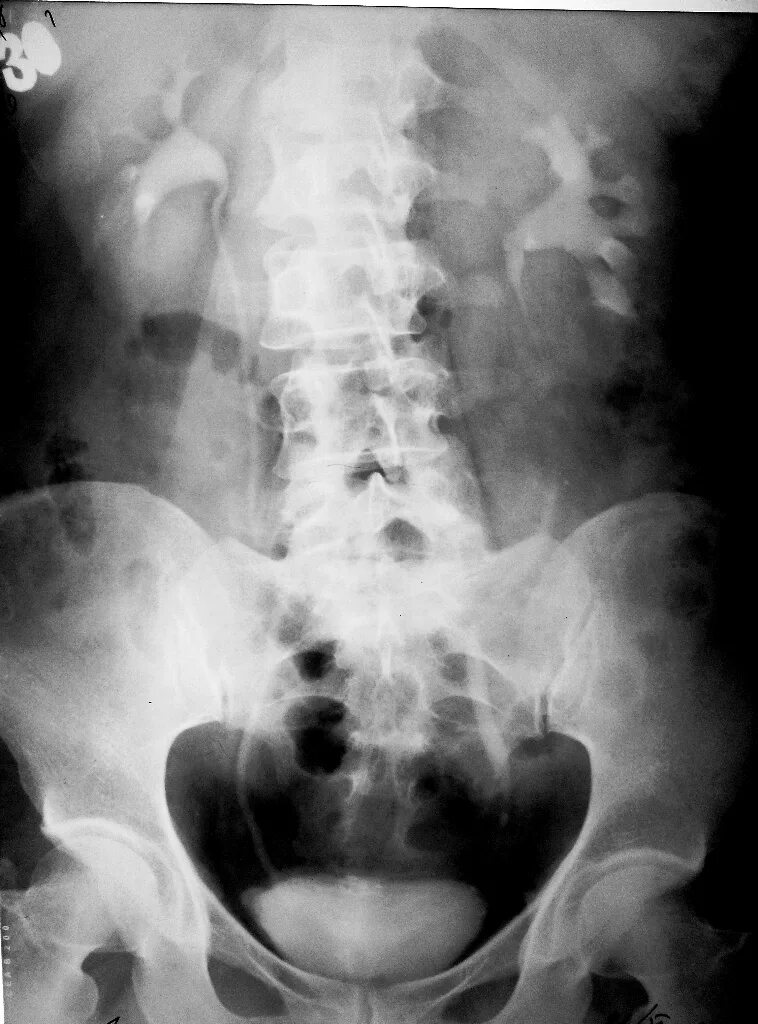

Урография с контрастом